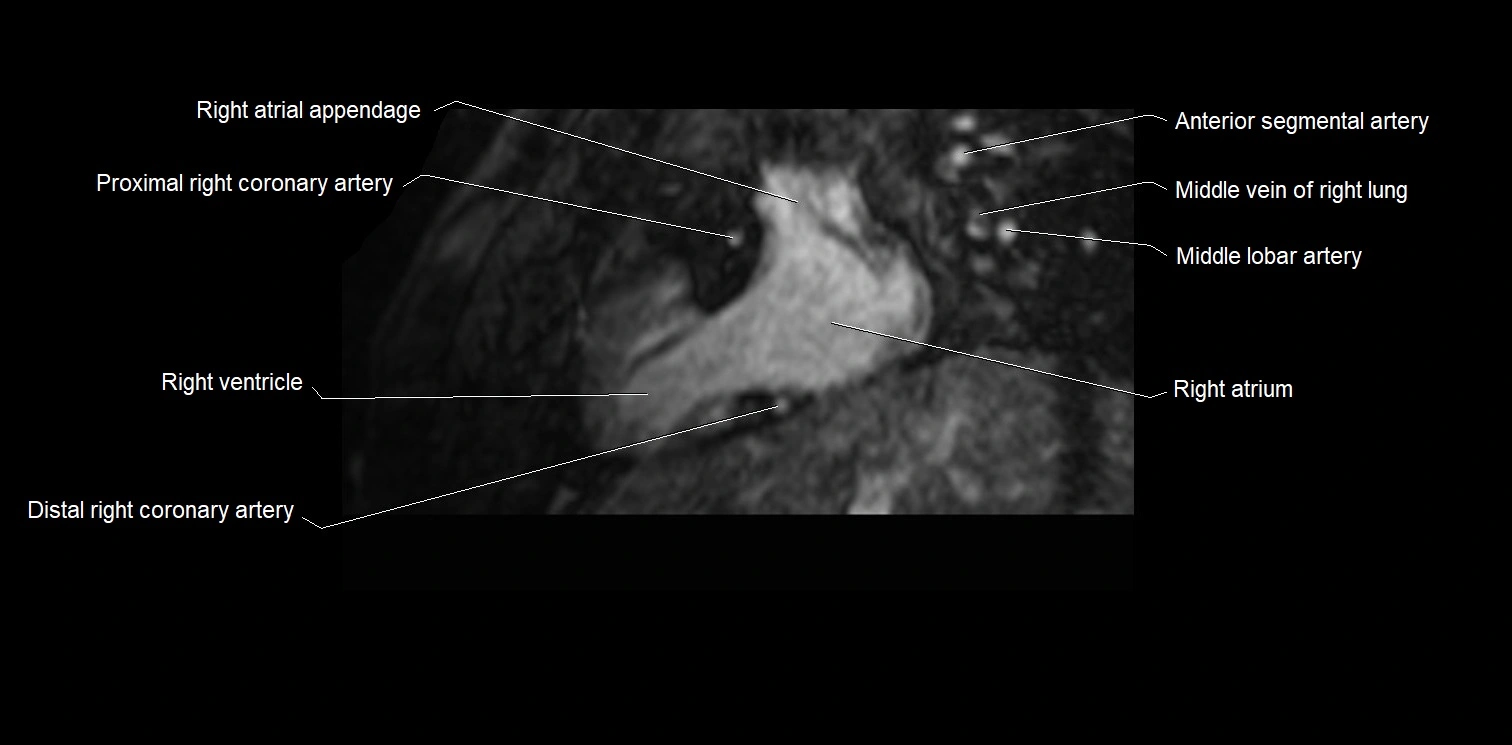

MRI image